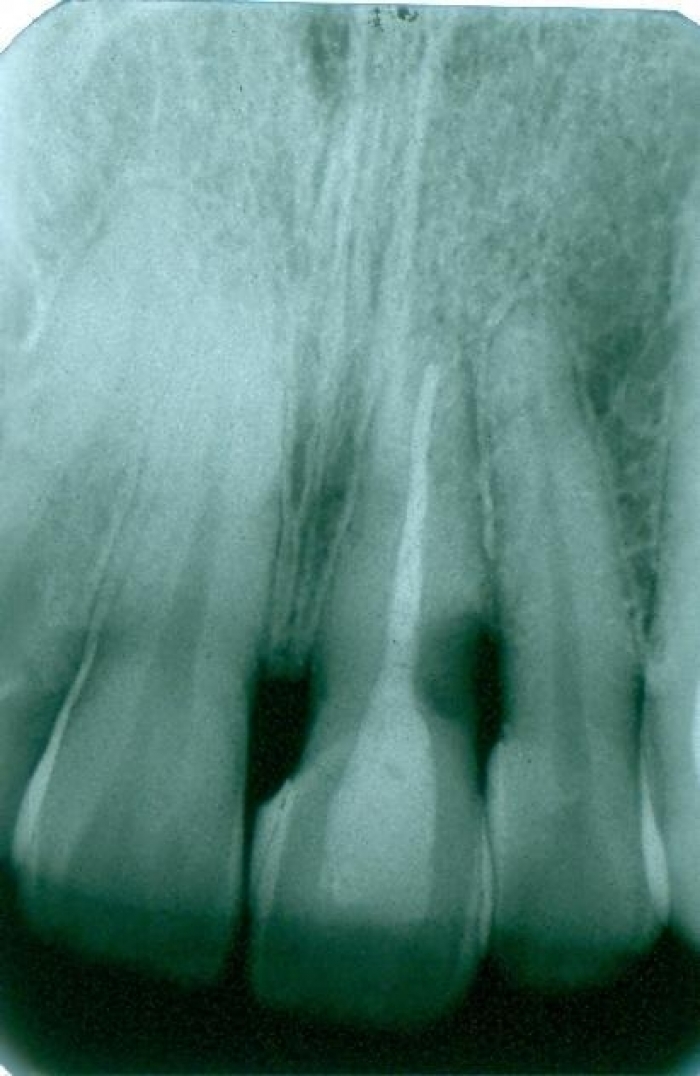

Rx Panoramico Inicial 15-06-15